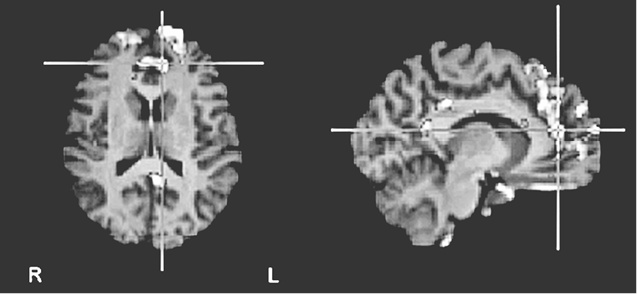

«Не уверен», как и предполагалось, активизировала переднюю поясную кору – своего рода нейронный сигнальный свет, вспыхивающий при внезапном появлении на горизонте чего-то нового и загадочного (рис. 8.1c (i) и (ii)).

Рис. 8.1c (i – вверху) и 8.1c (ii – внизу). Повышение активности во фронтальной части поясной извилины и в верхней лобной извилине при оценке утверждений, не поддающихся проверке («не уверен»). Рис. 8.1c (i) показывает разницу в активности по сравнению с картиной восприятия суждений, вызывающих доверие. Рис. 8.1c (ii) показывает разницу с картиной восприятия суждений, вызывающих недоверие (по материалам Харриса и др., 2008)